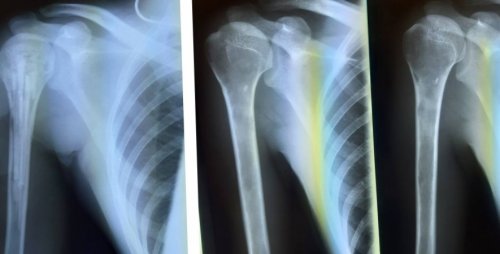

Диагностика